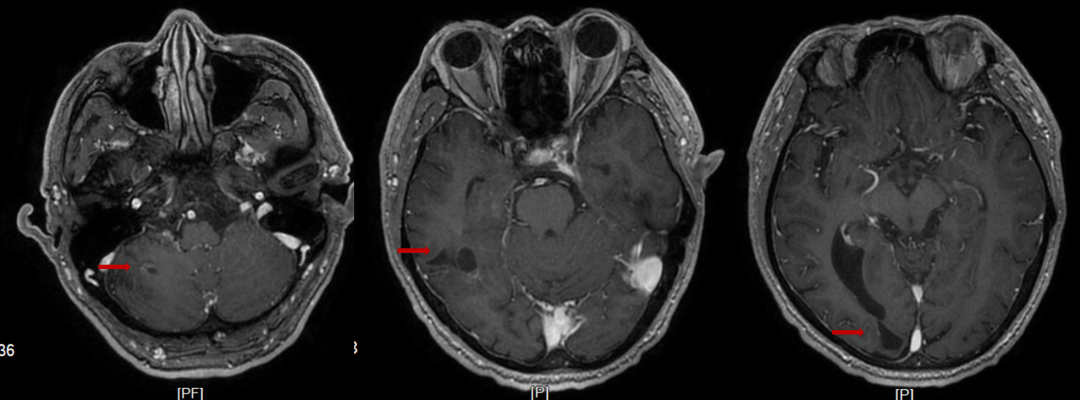

2022-08-04颅脑MRI:右侧小脑半球、右侧额颞顶枕叶及左侧放射冠区异常密度影,考虑多发占位性病变。

图1.首诊颅脑MRI

2023年3月21日(维持治疗4周期后)颅脑MRI:右侧小脑半球、右侧颞、枕叶及双侧侧脑室旁、右侧半卵圆中心多发异常信号,对比2023.01.02号片右侧小脑半球、右侧颞叶病灶有减小。

图5.治疗后颅脑MRI

图6.维持治疗后颅脑MRI

该患者就诊时为有症状脑转移患者,依据CSCO指南建议先行全脑放疗,症状稳定后再进行系统治疗。但该患者入院时头痛明显,烦躁,无法配合放疗体位固定,仅能接受紧急药物降颅压治疗,患者头胀痛减轻,但仍有言语不利、肢体活动不利,该患者一线使用斯鲁利单抗联合化疗的治疗方案,症状快速缓解,生活质量明显提高,一周期后水肿带消失。斯鲁利单抗联合化疗治疗3周期后,影像学显示,脑转移灶明显缩小,6周期治疗后脑转灶消失。既往研究显示,少有单纯化疗对脑转移灶产生良好的控制效果,此案例显示了斯鲁利单抗对脑转移患者具有良好的抗肿瘤疗效。ASTRUM-005研究中,纳入12.9%的基线伴脑转移患者,为同类研究中入组脑转移患者比例最多的临床研究,研究结果显示,斯鲁利单抗联合治疗组脑转移患者OS达13.9个月,而对照组仅为10个月,HR 0.61(95%CI 0.33-1.13)[7]